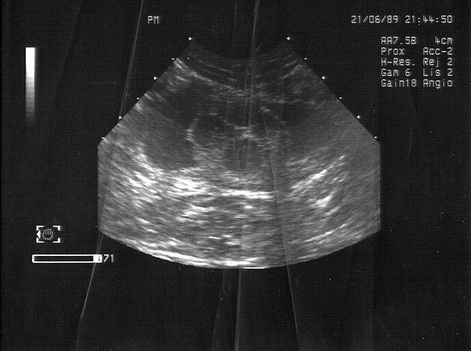

Avant de prescrire un traitement pour une cystite, le vétérinaire doit effectuer des analyses de sang et d'urine ainsi qu'une échographie afin d'exclure une lithiase urinaire. La vessie est également vidée à l'aide d'une sonde urinaire. Une fois le diagnostic de cystite posé, les propriétaires se demandent souvent : comment soigner un chat atteint de cette affection ? Certains se tournent immédiatement vers les forums à la recherche de remèdes traditionnels, tandis que d'autres consultent leurs voisins et amis. La plupart débutent le traitement avec le médicament Stop-Cystitis, mais le problème est que ce médicament ne fait que soulager les symptômes sans traiter la cause sous-jacente. Or, seuls ceux qui consultent un vétérinaire ont raison. Ce sont eux qui peuvent soigner leur animal le plus rapidement et le plus efficacement possible, en éliminant la cause de la maladie.